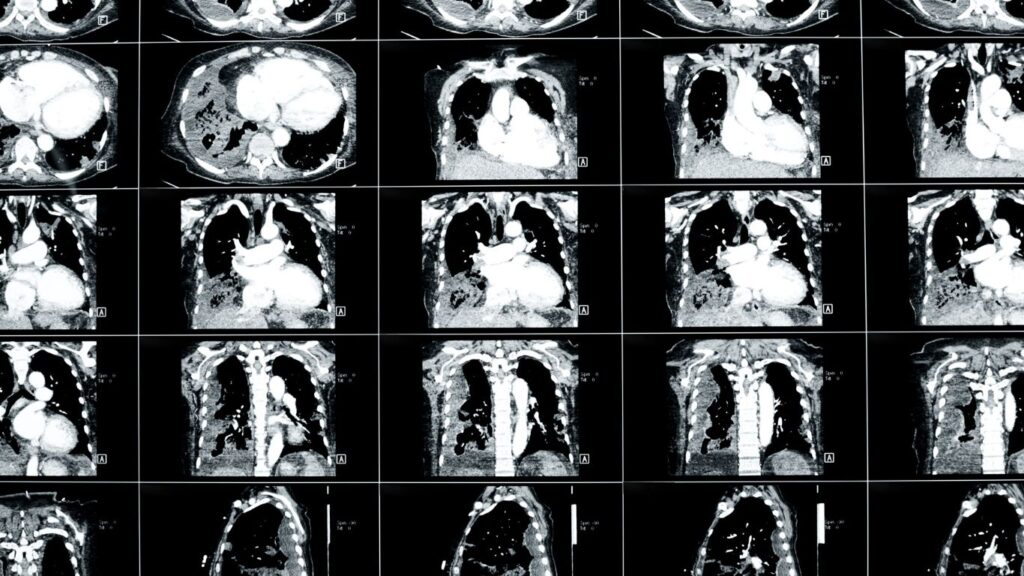

Tomografía Simple: Diagnóstico Preciso en Querétaro

La tomografía simple es un procedimiento médico fundamental que nos permite visualizar con precisión las estructuras internas del cuerpo humano. Este tipo de diagnóstico por imagen proporciona cortes transversales detallados, lo cual es esencial para identificar diversas patologías. En Querétaro, contamos con clínicas como Altaria, que utilizan tecnología avanzada para ofrecer a los pacientes un […]

Tomografía con contraste en Querétaro

La tomografía con contraste es un procedimiento esencial en el campo del diagnóstico médico que nos permite obtener imágenes detalladas de los órganos y tejidos del cuerpo. En Querétaro, ofrecemos este servicio en Altaria, donde garantizamos atención personalizada y el uso de tecnología de vanguardia. La precisión en el diagnóstico es crucial para determinar el […]